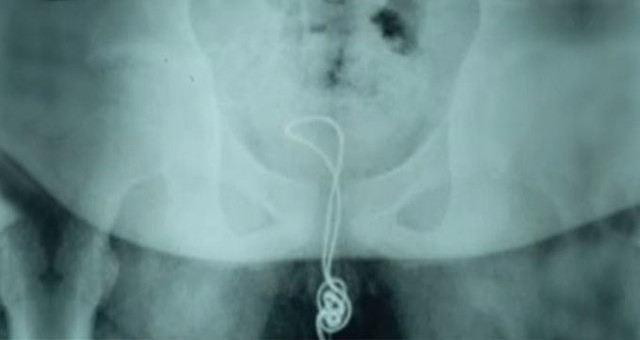

İlginç olay Çin'de yaşandı. 13 yaşındaki bir erkek çocuğun cinsel organına USB kablosu sıkıştı ve düğümlendi. Kabloyu geri çekemeyen çocuk, acı içinde hastaneye kaldırılıp ameliyata alındı.

ÇIKARAMAYINCA AİLESİNE SÖYLEMEK ZORUNDA KALDI;Adı açıklanmayan Çinli çocuk, cinsel organından içeri soktuğu kablonun mesanesinin içinde düğüm olması üzerine geri çıkaramadı. Yaklaşık 20 santimetrelik kablo yüzünden dayanılmaz derecede acı çeken çocuk, durumu ailesine söylemek zorunda kaldı.

MESANESİNİ KESEREK ÇIKARDILAR; Çin'in kuzey-doğu Heilongjiang eyaletindeki Linkou şehrindeki bir hastaneye kaldırılan çocuğun içinde düğümlenen kabloyu doktorlar da dışarı çıkarmayı başaramayınca tek çare olarak ameliyata alındı ve kablo mesanesinden çıkarıldı.